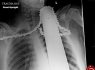

وحشتناک ترین عکس های رادیولوژی از بدن انسان+ تصاویر

در این مطلب می‌توانید معجزات پزشکی را در قالب تصاویر اشعه ایکس مشاهده کنید. آیا می‌توانید باور کنید که این افراد جان سالم به در برده‌اند؟